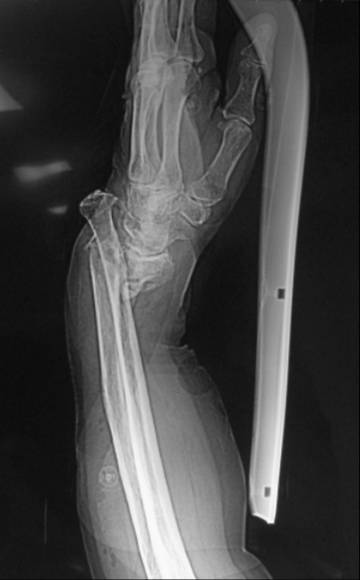

患者王某,老年女性,80岁,主因摔伤致左腕开放性骨折急症于2010年3月入院。查体:患者左侧腕关节处尺骨茎突哆出,掌侧皮肤裂伤,长约6cm,肌腱及皮下组织外露,左腕关节畸形。入院诊断为左侧腕关节开放伤(图1a);左侧桡骨远端骨折;左侧腕关节脱位(图1b)。于入院当日急症臂丛麻醉下行左腕伤口清创缝合术,左侧尺腕关节复位内固定术,左侧桡骨远端骨折复位内固定术(图2)。手术过程顺利,术后患者恢复良好,约术后5周拔除左侧腕关节固定克氏针,后患者自动出院。出院后1日患者因突发喘憋,进行性加重再次就诊于我院,血气分析示PO2 36.3mmHg,PCO2 30.4mmHg,D-二聚体4000ng/ml,胸CT示左下肺大片高密度影,肺通气灌注扫描显像提示双肺多发节段灌注缺损。入院诊断为:I型呼吸衰竭;肺栓塞;冠心病;高血压病3级;糖尿病2型;左桡骨远端骨折。给予速碧林 4100IU/d经验性抗凝治疗。第2日患者喘憋症状明显缓解,自诉无呼吸困难,动脉氧分压升至141mmHg(鼻导管吸氧5L/分)。应用速碧林3日后加用华法令5mg /d,间断复查KPTT及INR,华法令与速碧林重叠应用5日后,患者PT延长至18.9s,即停用速碧林,单独应用华法令,1周后患者好转出院。

图1 a、左侧腕关节处尺骨茎突哆出,掌侧皮肤裂伤,长约6cm,肌腱及皮下组织外露,左腕关节畸形。